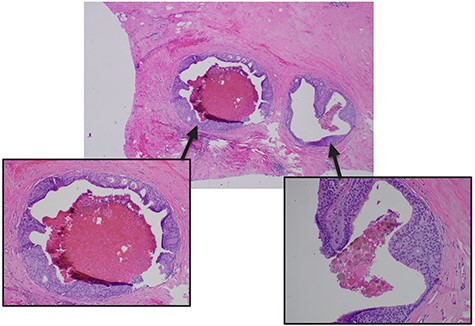

The patient underwent surgery <1 month after initial diagnosis. The surgery proceeded as planned without complications and was well tolerated by the patient. Perioperative management followed the institution-wide opioid-sparing enhanced recovery after (breast) surgery protocol, affording our patient a safe discharge home on postoperative Day 1. Final surgical pathology confirmed bilateral presence of intermediate grade (non-comedo) DCIS with (at least) 3-mm clear margins and negative node involvement (Figs 3, 4), yielding a favorable diagnosis of Tis N0 M0 (Stage 0) disease.

Pathologic microscopy of right breast ductal carcinoma in situ with magnified images highlighting absence of local invasion.